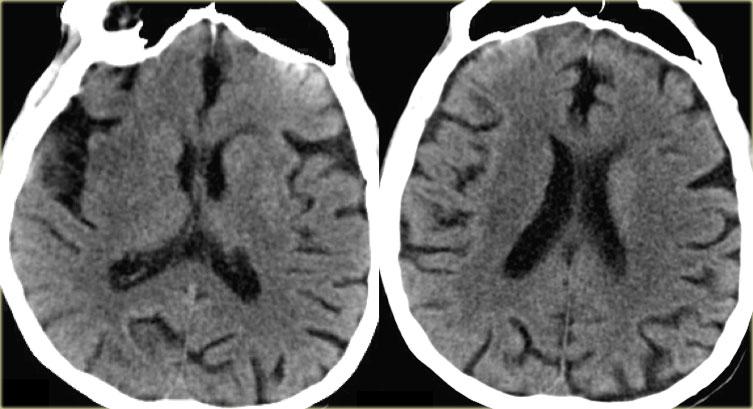

Trong trường hợp bên trái, đầu tiên CT không tiêm thuốc được thực hiện.

Nếu có xuất huyết, thì không cần thực hiện thêm khảo sát nào.

Trong trường hợp này, CT bình thường và CTP được thực hiện, cho thấy khiếm khuyết tưới máu.

CTA sau đó được thực hiện và phát hiện bóc tách động mạch cảnh trong trái.